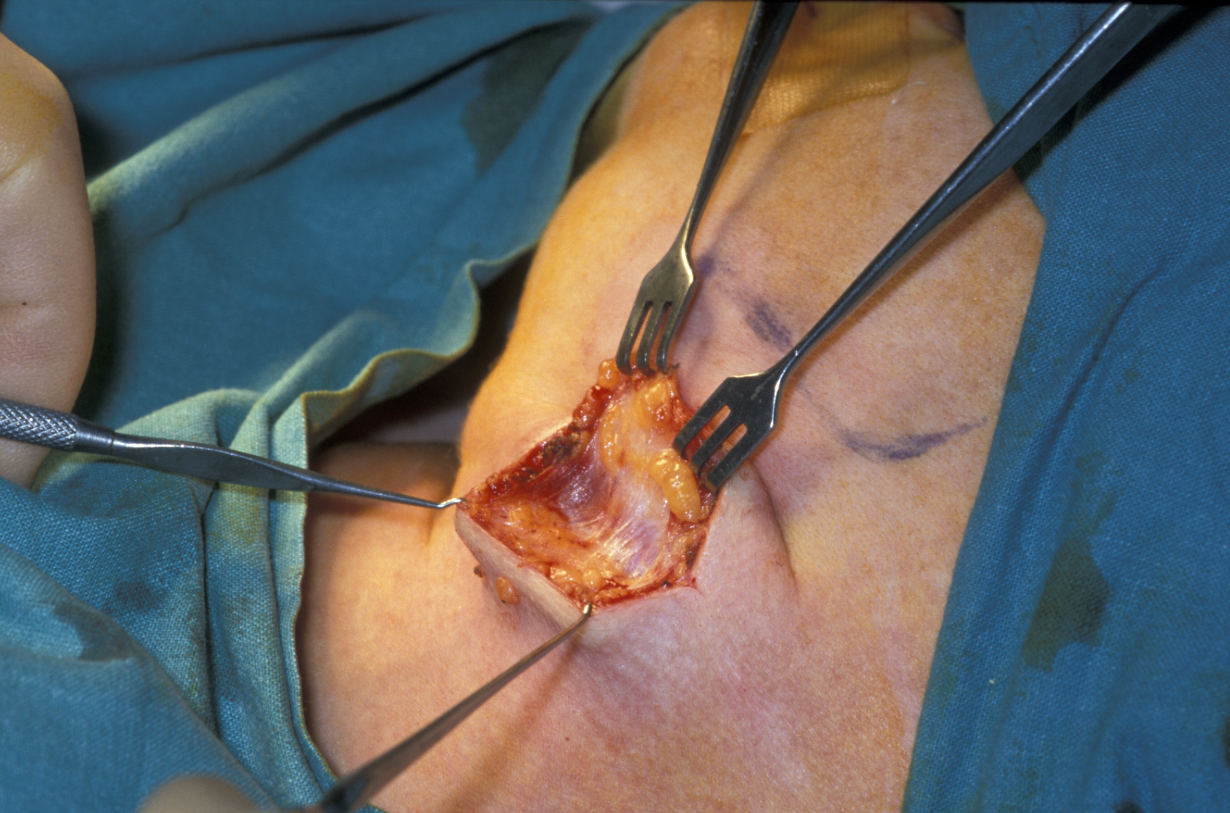

Submandibular gland excision is required after the gland has suffered irreparable damage from infection and/or obstructive disease. The surgical approach is by trans-cervical (from the neck) approach. The incision is two finger-breadths below the lower border of the mandible. A 3 to 4 cm incision is made. The incision is then deepened through fat that bleeds; bleeding needs to be controlled using bipolar diathermy to expose the platysma muscle (a broad sheet of muscle covering front and sides of the neck; see Figure 5).

Figure 5: Submandibular gland excision. The incision is two finger-breadths below the lower border of the mandible. After skin incision, control of bleeding and sweeping aside fat, the platysma muscle is exposed.